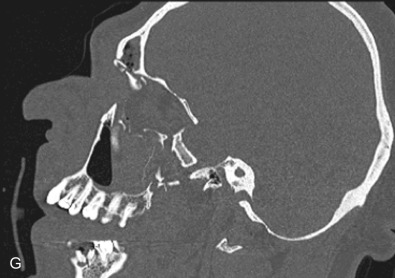

The gold standard for radiographic evaluation is thin-slice helical computed tomography (CT). Midface fractures are confirmed by axial, coronal, and sagittal views. The degree of comminution, bone loss, and detailed images of the fracture patterns can be assessed and juxtaposed to surrounding soft tissue structures. 3D reconstruction, when utilized, can aid in visualizing the complex 3D anatomical orientation of fracture fragments that occur in Le Fort injuries and facilitate reconstructive planning.

Le Fort II fractures are pyramidal in shape, involving the central portion of the midface while the lateral orbits and zygoma remain intact. The line of fracture extends bilaterally through the nasofrontal junction, medial orbital wall, inferior orbital rim, along the maxilla, through the dental alveolus anteriorly and posteriorly at the level of the maxillary tuberosity into the pterygoid plates ( Figs. 1.13.14 and 1.13.15 ). Only Le Fort II fractures violate the inferior orbital rim, causing the highest incidence of infraorbital nerve hypesthesia due to the proximity to the infraorbital foramen. Bones of the maxilla below the Le Fort II line of fracture can be intact, however they are often comminuted with other fracture patterns occurring in the Le Fort II segment. The force is typically delivered centrally at the level of the nasal bones, resulting in the separation of the central maxilla from the surrounding facial skeleton. Brain injuries are more frequent in central Le Fort II injury patterns.